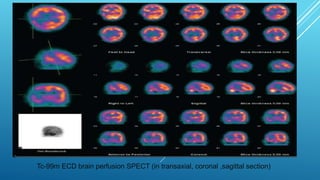

This document provides information about brain perfusion SPECT imaging, including: - It uses radiopharmaceuticals like Tc-99m HMPAO and Tc-99m ECD that cross the blood-brain barrier and distribution corresponds to regional cerebral blood flow. - It is used to evaluate conditions like dementia, head injuries, cerebrovascular disease, and inflammation. - Contraindications include pregnancy and non-cooperative patients. - Patient preparation involves a quiet environment during radiotracer injection and uptake.